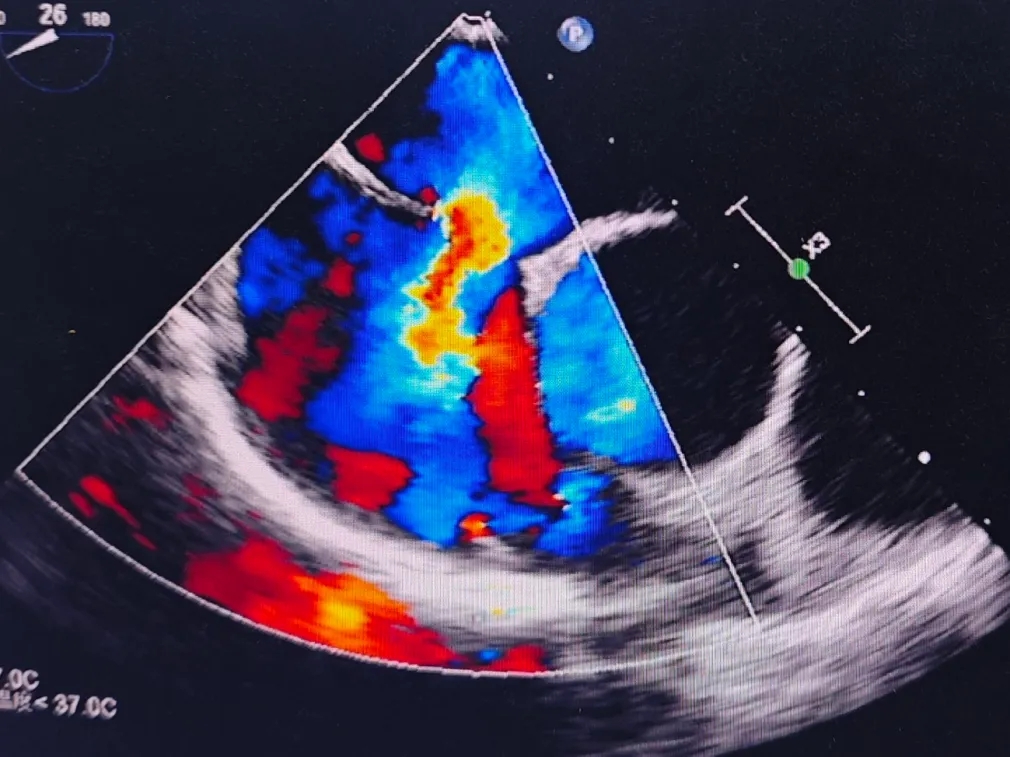

经食道超声描述:房间隔总长42mm,房间隔中部可见回声脱失约15mm,缺损距二尖瓣环约17mm,距离上腔静脉约9mm,主动脉侧残端约3mm。CDFI: 房水平见左向右分流信号。

超声提示:房间隔缺损(中央型),房水平左向右分流

术前食道超声可见房水平左向右分流